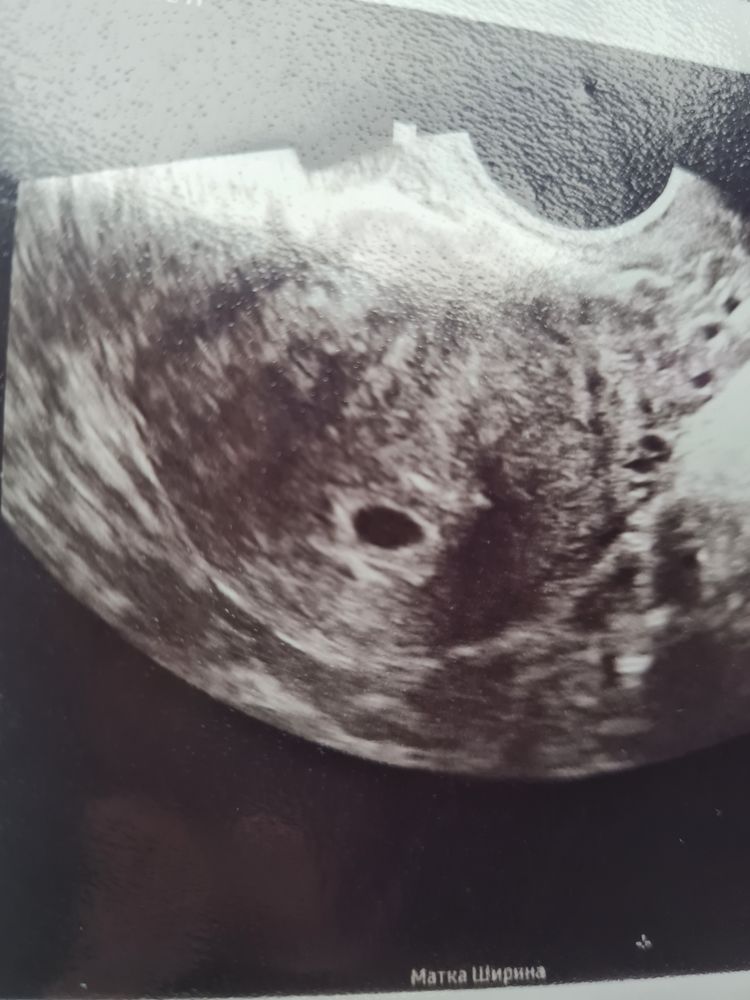

Фото узи 4 н 3 дня, что видно ?

У вас точно 4 недели и 3 дня? На таком сроке не видно эмбрион. Да и пя не таких размеров, если вообще видно его

Ari A, ваш срок соответствует 6 неделям где-то да.

да, четко видно эмбрион